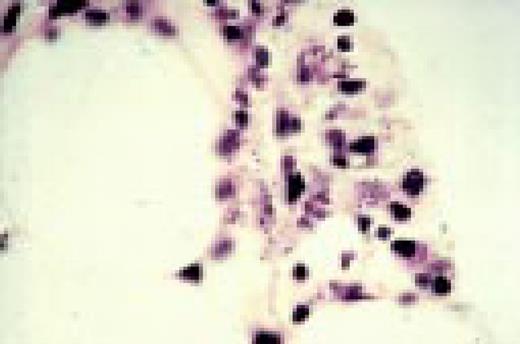

Slide L51

Leishmaniasis associated with AIDS, bone marrow biopsy. Leishmania donovani are noted in macrophages. These parasites are similar in size to Histoplasma capsulatum, but the “double dot” appearance of the nucleus and kinetoplast is apparent in Leishmania (see center).FIG51